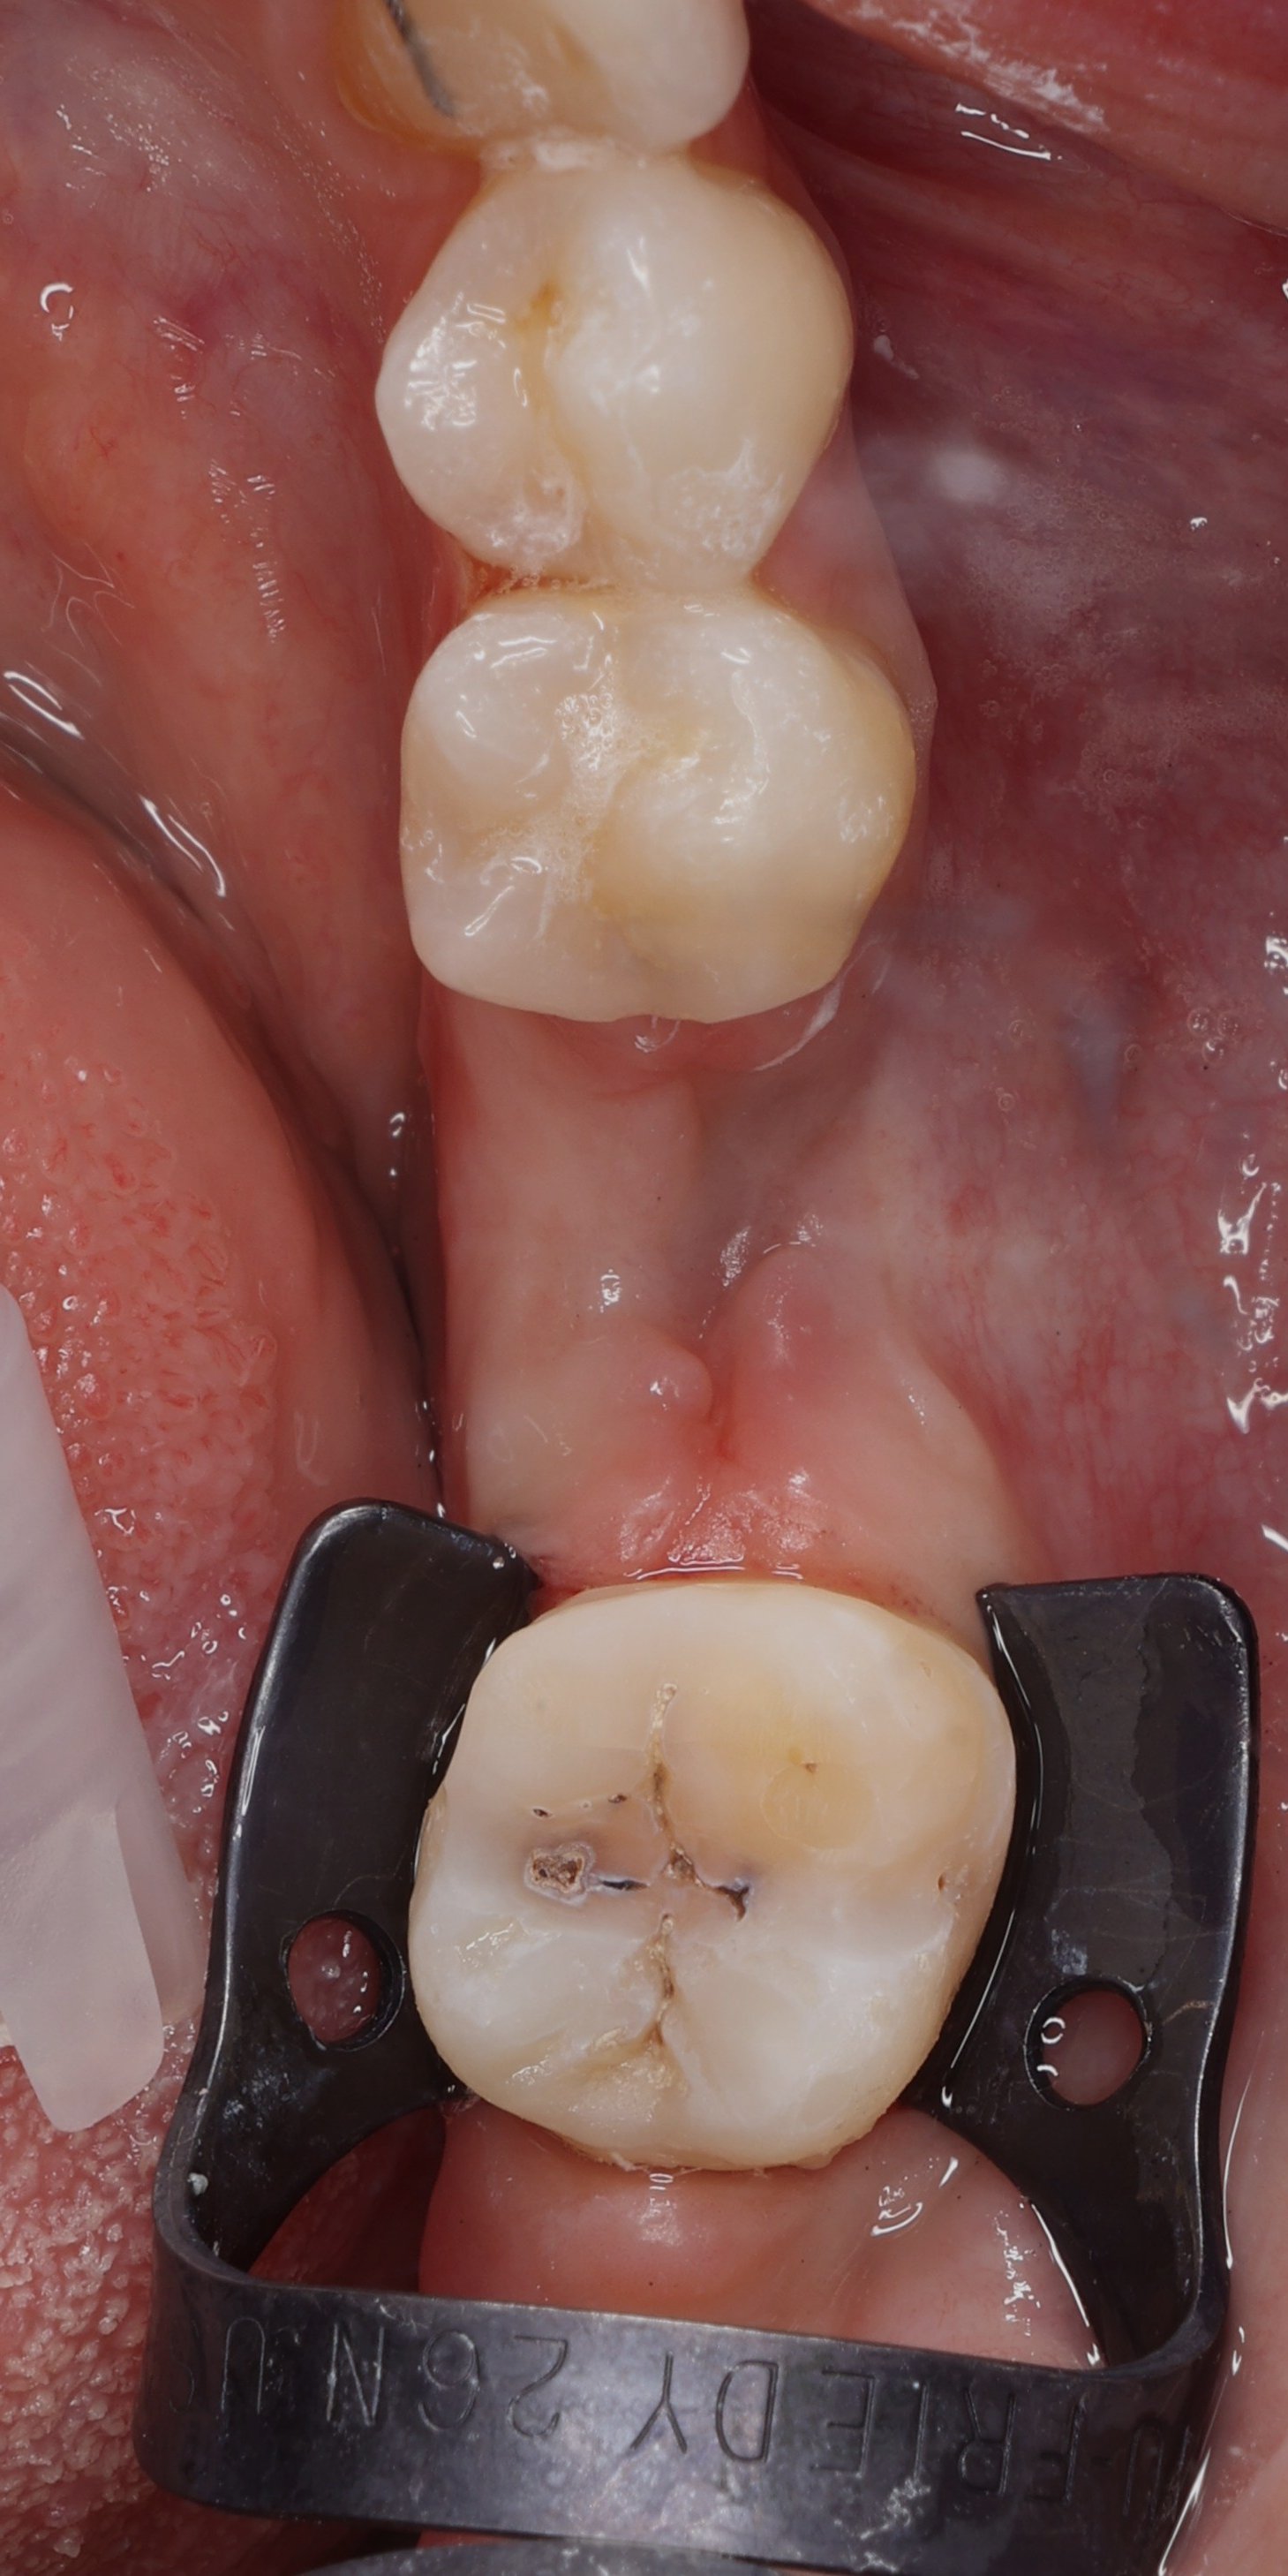

Relativement récents, les bridges collés cantilever postérieurs constituent une alternative fixe, fiable et véritablement minimalement invasive aux implants dans les secteurs postérieurs. Cette thérapeutique qui repose sur des indications bien précises est parfois débattue avec passion sur les réseaux sociaux ou dans les congrès scientifiques. Cependant des études cliniques existent, tout comme des recommandations validées dans des journaux internationaux. Leur succès repose sur des préparations et des principes biomécaniques rigoureux, pourtant simples à intégrer au quotidien. Cette intervention propose un guide clair et opérationnel incluant indications, étapes clés, protocoles d’adhésion et réglages occlusaux pour les mettre en œuvre avec confiance et reproductibilité.